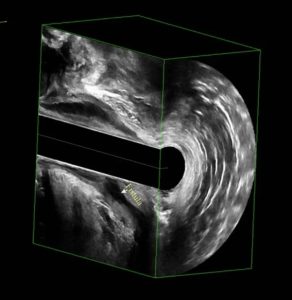

- Görüntüleme yöntemleri (özellikle derin veya karmaşık apselerde):

- Anal ultrason (USG): Apsenin derinliğini ve sfinkterlerle ilişkisini gösterir.

- Manyetik Rezonans (MR): Özellikle tekrarlayan, derin veya fistül şüphesi olan olgularda altın standarttır; cerrahi planlamayı yönlendirir

Anal apseler, yerleştikleri anatomik bölgeye göre sınıflanır: Park’s Sınıflamsı

- Perianal apse: En sık tip; makatın hemen yanında, deride yer alır.

- İsüyiorektal apse: Makat kaslarının daha derinindeki boşlukta oluşur.

- İntersfinkterik apse: İç ve dış makat kasları arasında gelişir.

- Supralevator apse: Daha yukarıda, kasların üst seviyesinde, nadir ama ciddi seyirli apse.

Bu sınıflama, hangi cerrahi yaklaşımın seçileceği açısından önemlidir.